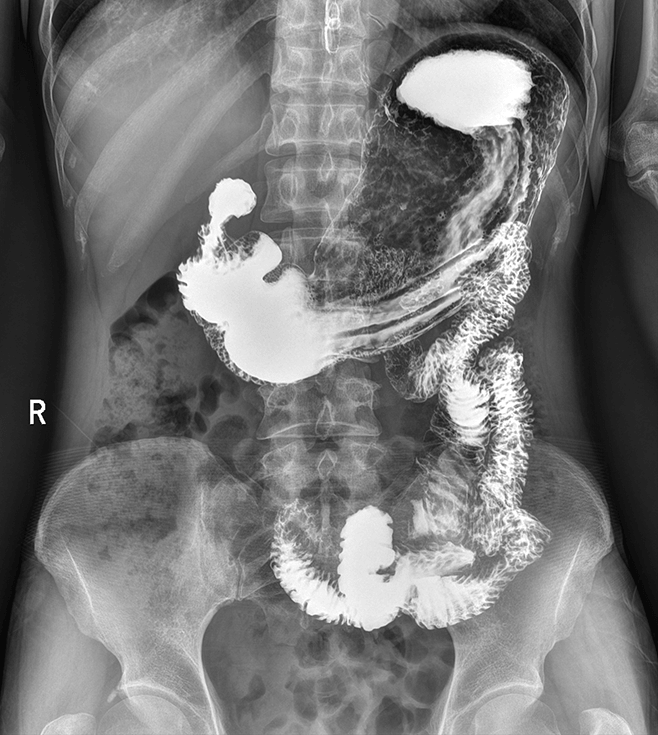

多功能诊断专用动态DR

太阳成集团tyc122cc入口科技全新设计的第四代床式动态DR,集拍片、透视、造影、全身拼接、尘肺体检于一体,一机多能,真正意义上实现全科室应用,提升医院实际效益。

高清动态平板探测器

搭载自主研发超清大视野动态平板探测器,600微米碘化铯大幅提升X线转化效率,独特的非晶硅阵列与高速读取集成电路紧密协作,轻松实现多帧率透视与高清点片。

专业的影像处理系统

“腾灵”系列搭载的IEAE影像处理系统,具备多项发明专利。本系统采用多频域图像处理技术,其6大核心处理模块使影像具有优秀的一致性、柔和性、空间层次感和纹理细腻度,为用户精准诊断病灶奠定了坚实的基础。